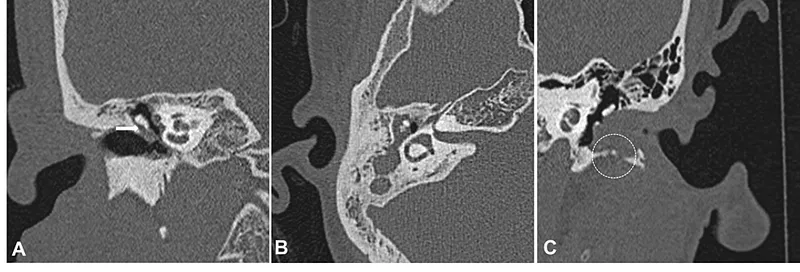

- CT Scan (HRCT Temporal Bone):

- Assesses bony erosion (scutum, ossicles, tegmen, sigmoid plate).

- Shows extent of soft tissue mass.

⭐ HRCT temporal bone is the gold standard imaging for assessing bony erosion and extent of cholesteatoma.

- MRI (DW-MRI): Differentiates cholesteatoma from granulation tissue or cholesterol granuloma, especially in post-operative recurrence. Useful if CT is equivocal.